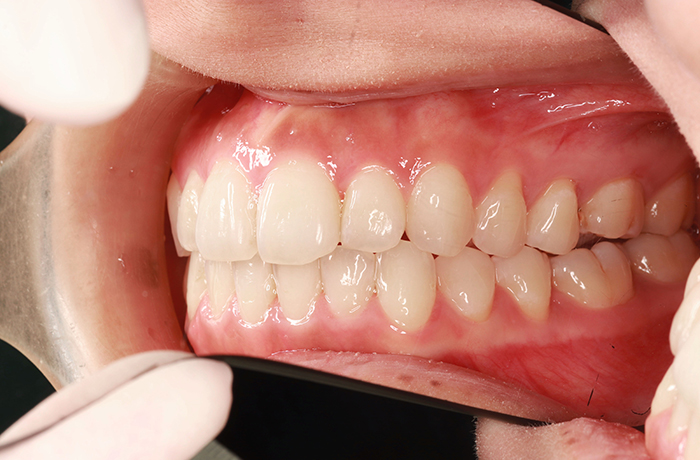

K様

治療前

年齢 27歳

性別 女性

治療名称 マウスピース型カスタムメイド矯正歯科装置(インビザライン)・コンプリヘンシブパッケージ(フルパッケージ)

総額治療費用 770,000円(税込10%) 金額備考 精密検査料・診断料 33,000円(税込10%)

治療期間 1年11か月 通院頻度など 40日ごと

1枚につき10日装着を指示しました。

治療内容

患者の症状 上顎前歯の前突、八重歯

治療方法 上下左右の第一小臼歯抜歯で、マウスピース型カスタムメイド矯正歯科装置による矯正

治療結果 上顎前歯の前突、八重歯が改善されました。

歯並びをより良くするために追加でアライナーを発注しました。

リスク/副作用 決められた時間装着する必要があります。